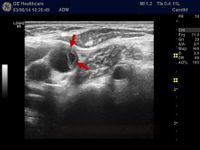

Recurring nosebleeds, headaches, and visual disturbances are common symptoms in patients with symptomatic hyperviscosity.16 Funduscopy is an important indicator of clinically relevant hyperviscosity. Among the first clinical signs of hyperviscosity are the appearance of peripheral and midperipheral ...

The first assessment is a physical examination for signs of a tendency to bleed – bruises on the skin, blood blisters in the mouth or the back of the eye. It is important to view the retina at the back of the · eye using an instrument known as an ophthalmoscope. Classical changes include sausage-shaped blood · vessels and small bleeds on the retina. It is also important to assess the functioning of vital organs, ... viscosity (PV), as well as the other routine tests of kidney and liver function.